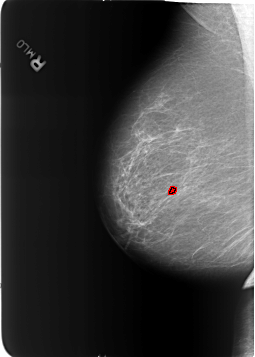

B_3211_1.RIGHT_MLO

FILE: B_3211_1.RIGHT_MLO.OVERLAY

TOTAL_ABNORMALITIES 1

ABNORMALITY 1

LESION_TYPE CALCIFICATION TYPE COARSE DISTRIBUTION N/A

ASSESSMENT 2

SUBTLETY 5

PATHOLOGY BENIGN_WITHOUT_CALLBACK

TOTAL_OUTLINES 1

BOUNDARY